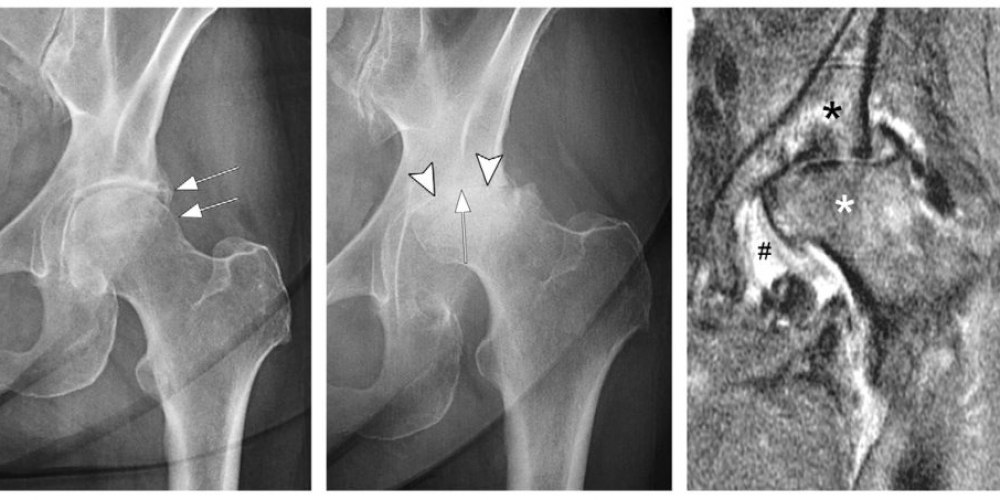

ACUTE DESTRUCTIVE HIP SEPTIC ARTHRITIS IN A YOUNG ADULT PATIENT CASE

From www.researchgate.net

53 years old male patients who had hip arthritis secondary to septic Hip Arthritis Disability arthritis can cause disability by limiting your mobility, fatigue, and work ability. learn about the criteria, process and tips for applying for ssdi or ssi benefits if you have rheumatoid arthritis or other types of. learn how to apply for social security disability if your osteoarthritis is severe and prevents you from working. Learn about the different. Hip Arthritis Disability.